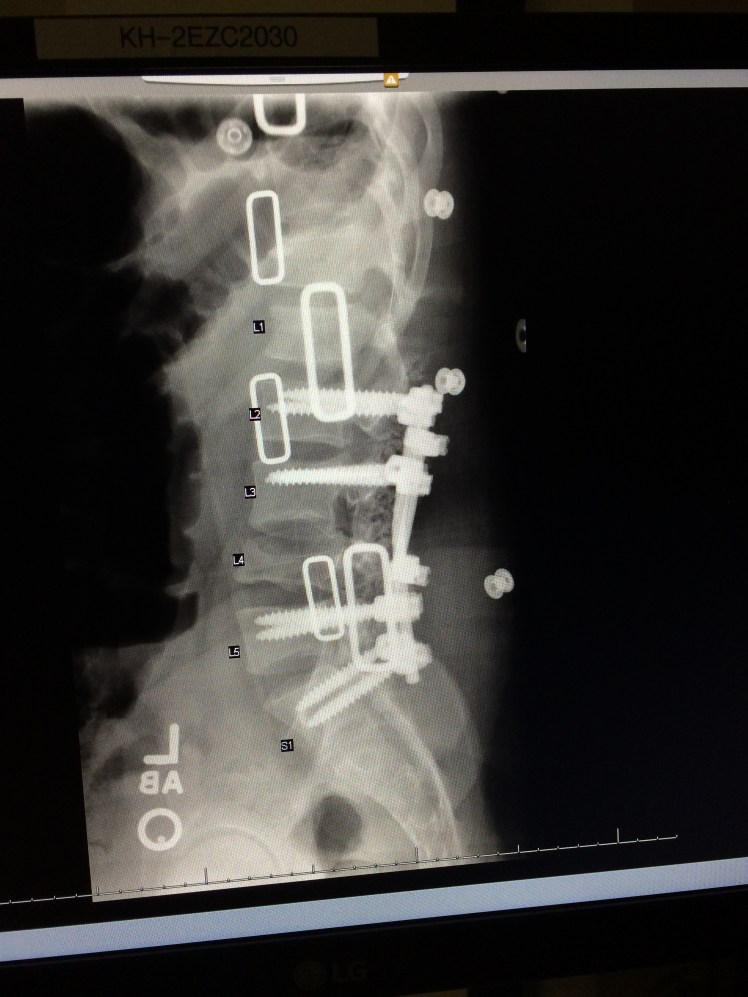

I spent eight days in KMC. Two days after the fall I had surgery. They got me in there, flipped me over and split my back open. I got eight screws and two rods. My ankle also had a hairline fracture.

So I had one 7-hour surgery. I burst fractured my L4, which required eight titanium screws and two titanium rods.